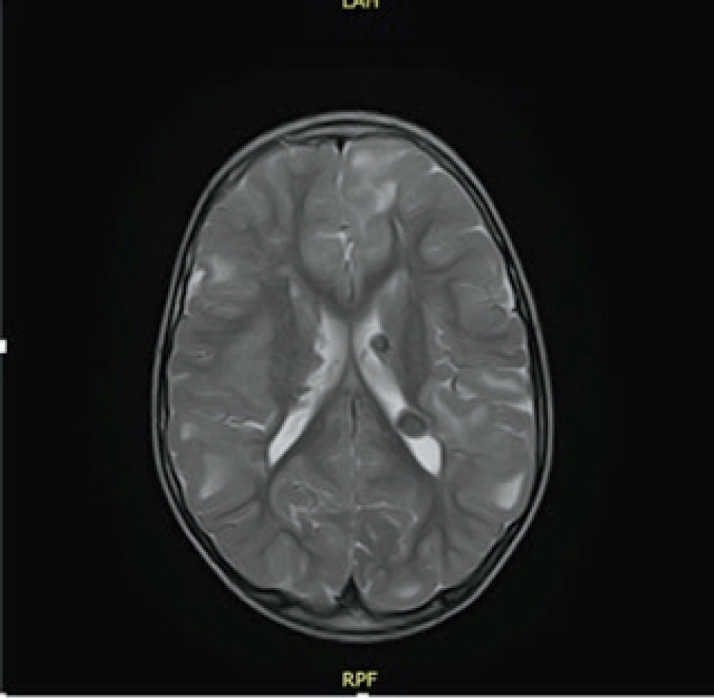

Case presentation: In this case report, we describe a seven year old patient with the clinical manifestation of TSC that includes supratentorial changes, subependymal hamartomas and angifibromas in the facial area. Besides the brain and skin changes, no other TSC characteristics were observed. The patient was referred to molecular genetic testing using Next Generation Sequencing (NGS). Results: Clinical exome sequencing revealed intronic TSC2 c.4849+2T>G variant. The variant was confirmed using Sanger sequencing on the subject. However, the variant was not detected in the parents, which indicated that it arose de-novo. The RegSNP-intron, Mutation Taster and Human Splicing Finder were used as a bioinformatic tools to predict the possible effect on protein. Using bioinformatic tools, it was determined that the variant is possibly damaging to protein.